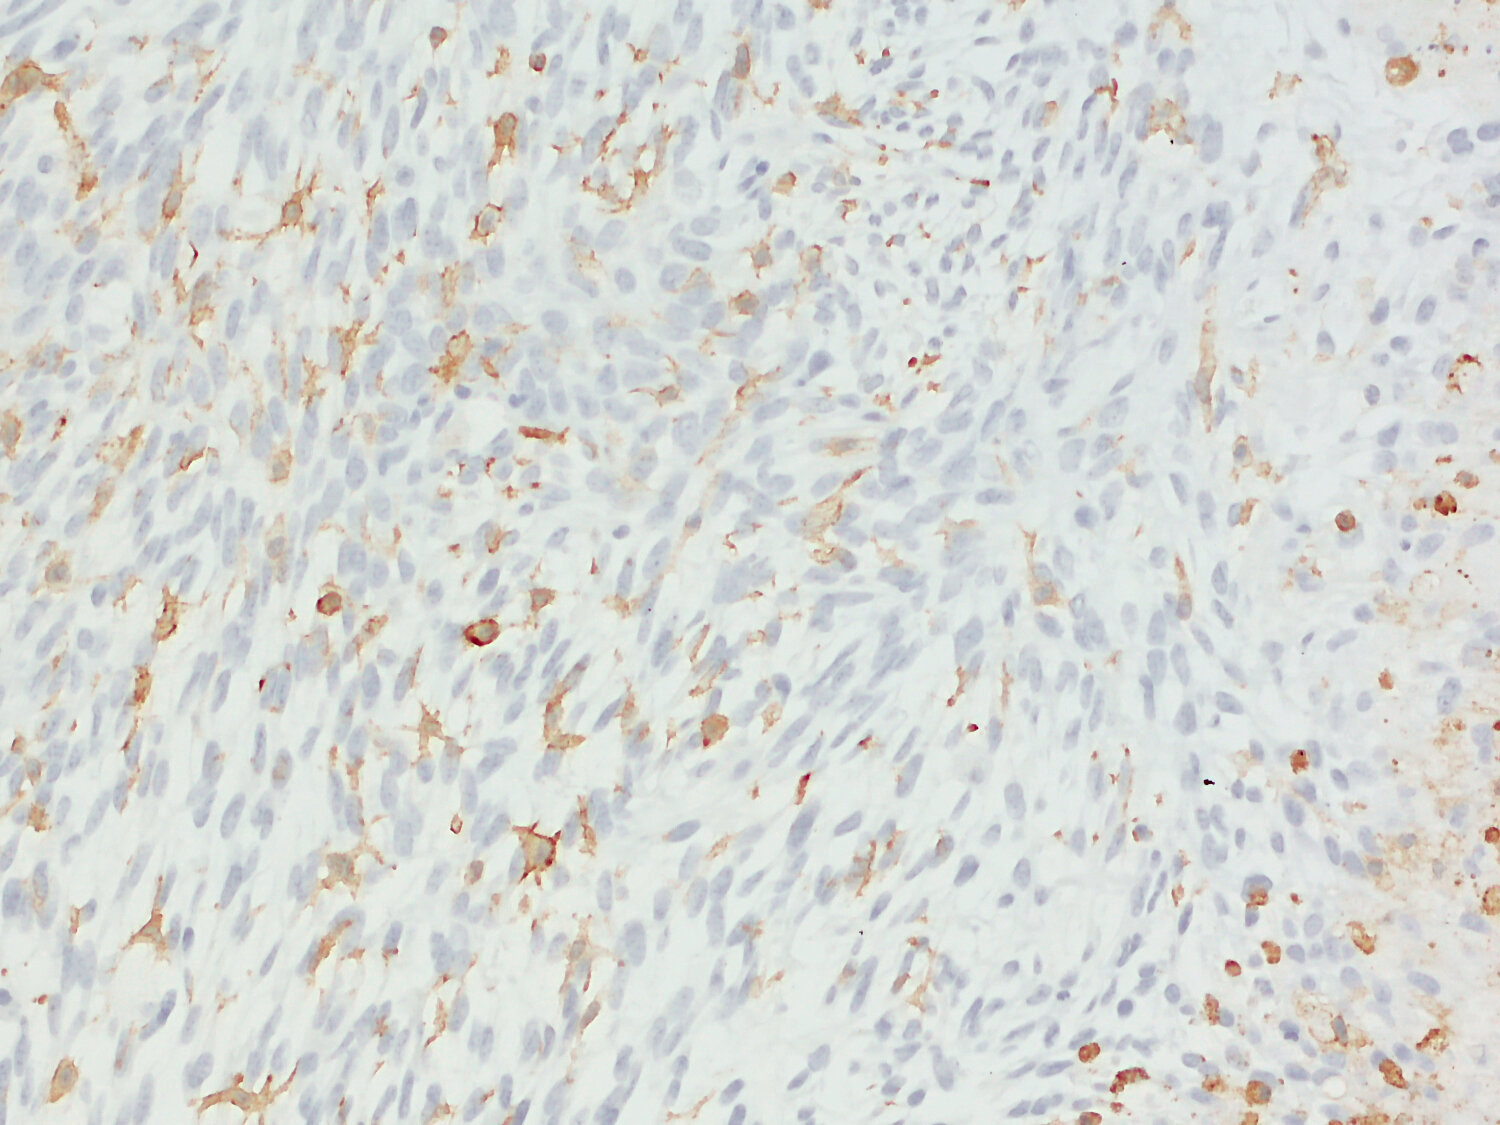

Increased CD11b expression represents microglial activation in virus infected mouse brain

IHC-P: 1 : 1000 gallery

Immunohistochemistry (IHC-P) of formalin fixed, paraffin embedded (FFPE) tissue (some antibodies require special antigen retrieval steps, please refer to the ”Remarks” section). Immunoreactivity is usually revealed by fluorescence or a chromogenic substrate.